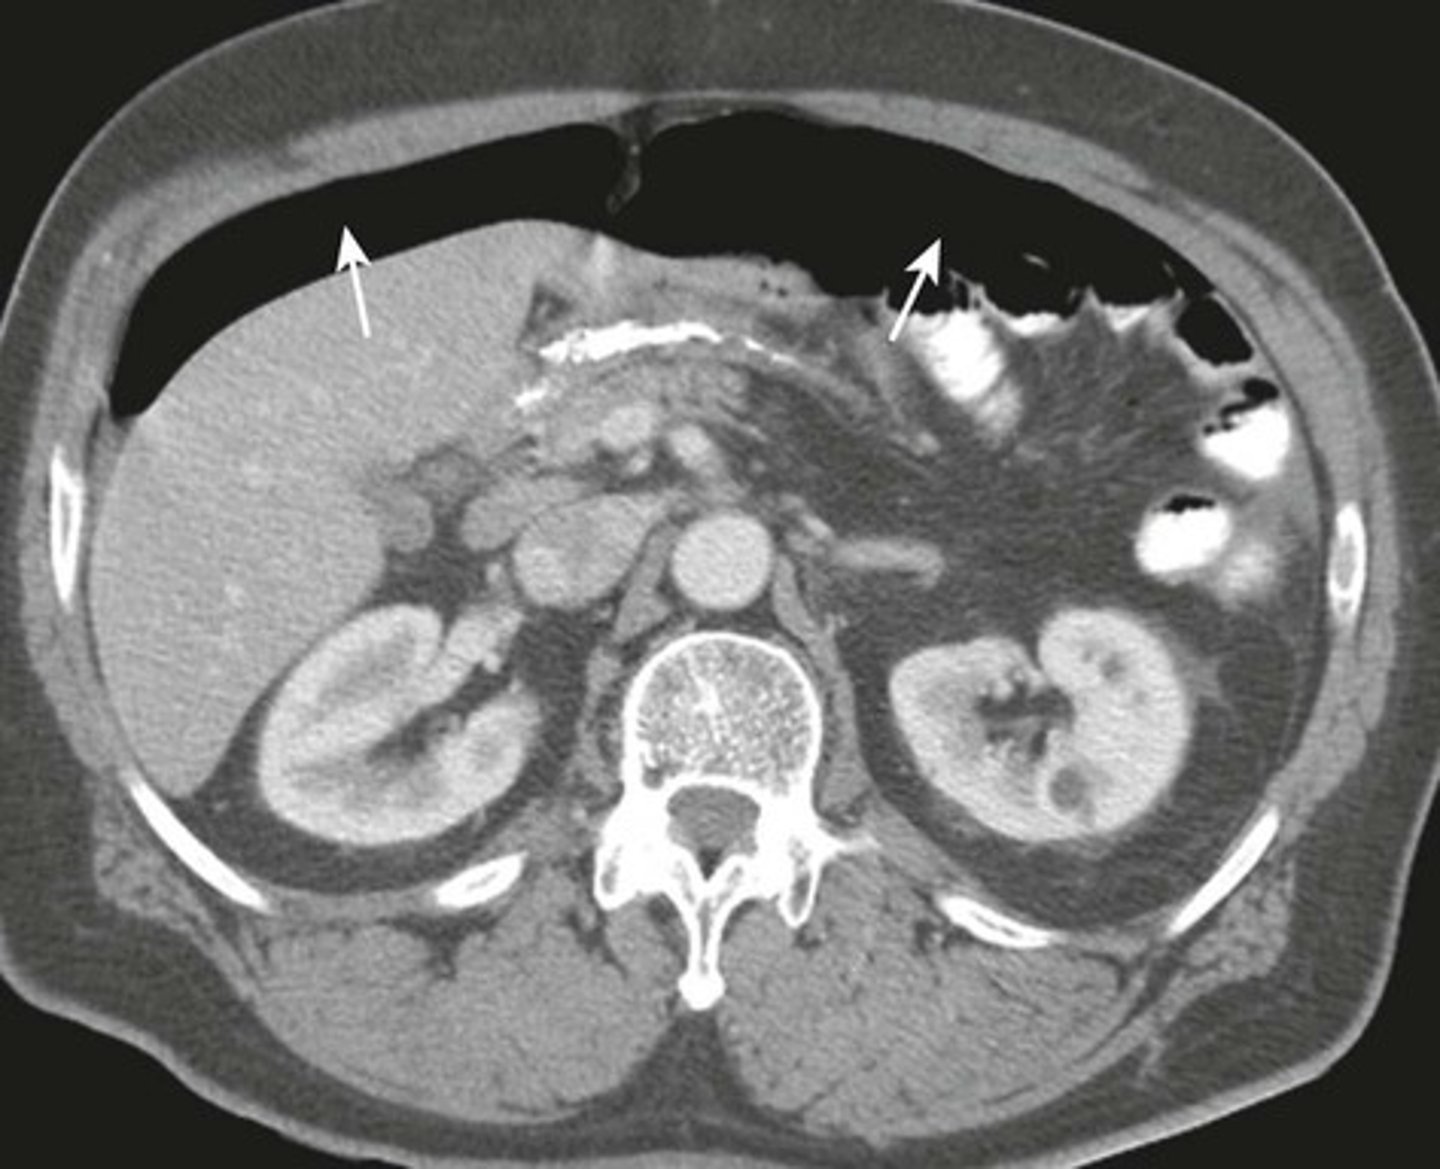

Normal Kidneys

K: Kidneys, lie in the renal fossae

DOTTED BLACK ARROWS: Central portion of the kidneys, should contain fat in a normal renal pelviz.

SOLID BLACK ARROW: Right renal artery, running posterior to the IVC

DOTTED WHITE ARROW: Left renal vein, lies anterior to the left renal artery.

SOLID WHITE ARROW: left renal artery.

A: Abdominal Aorta

IVC: inferior vena cava